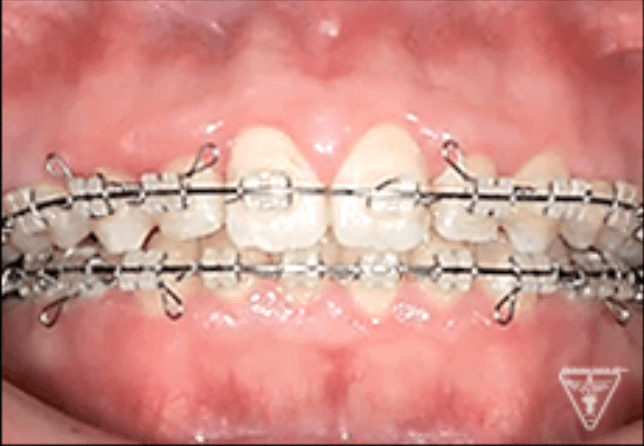

初期